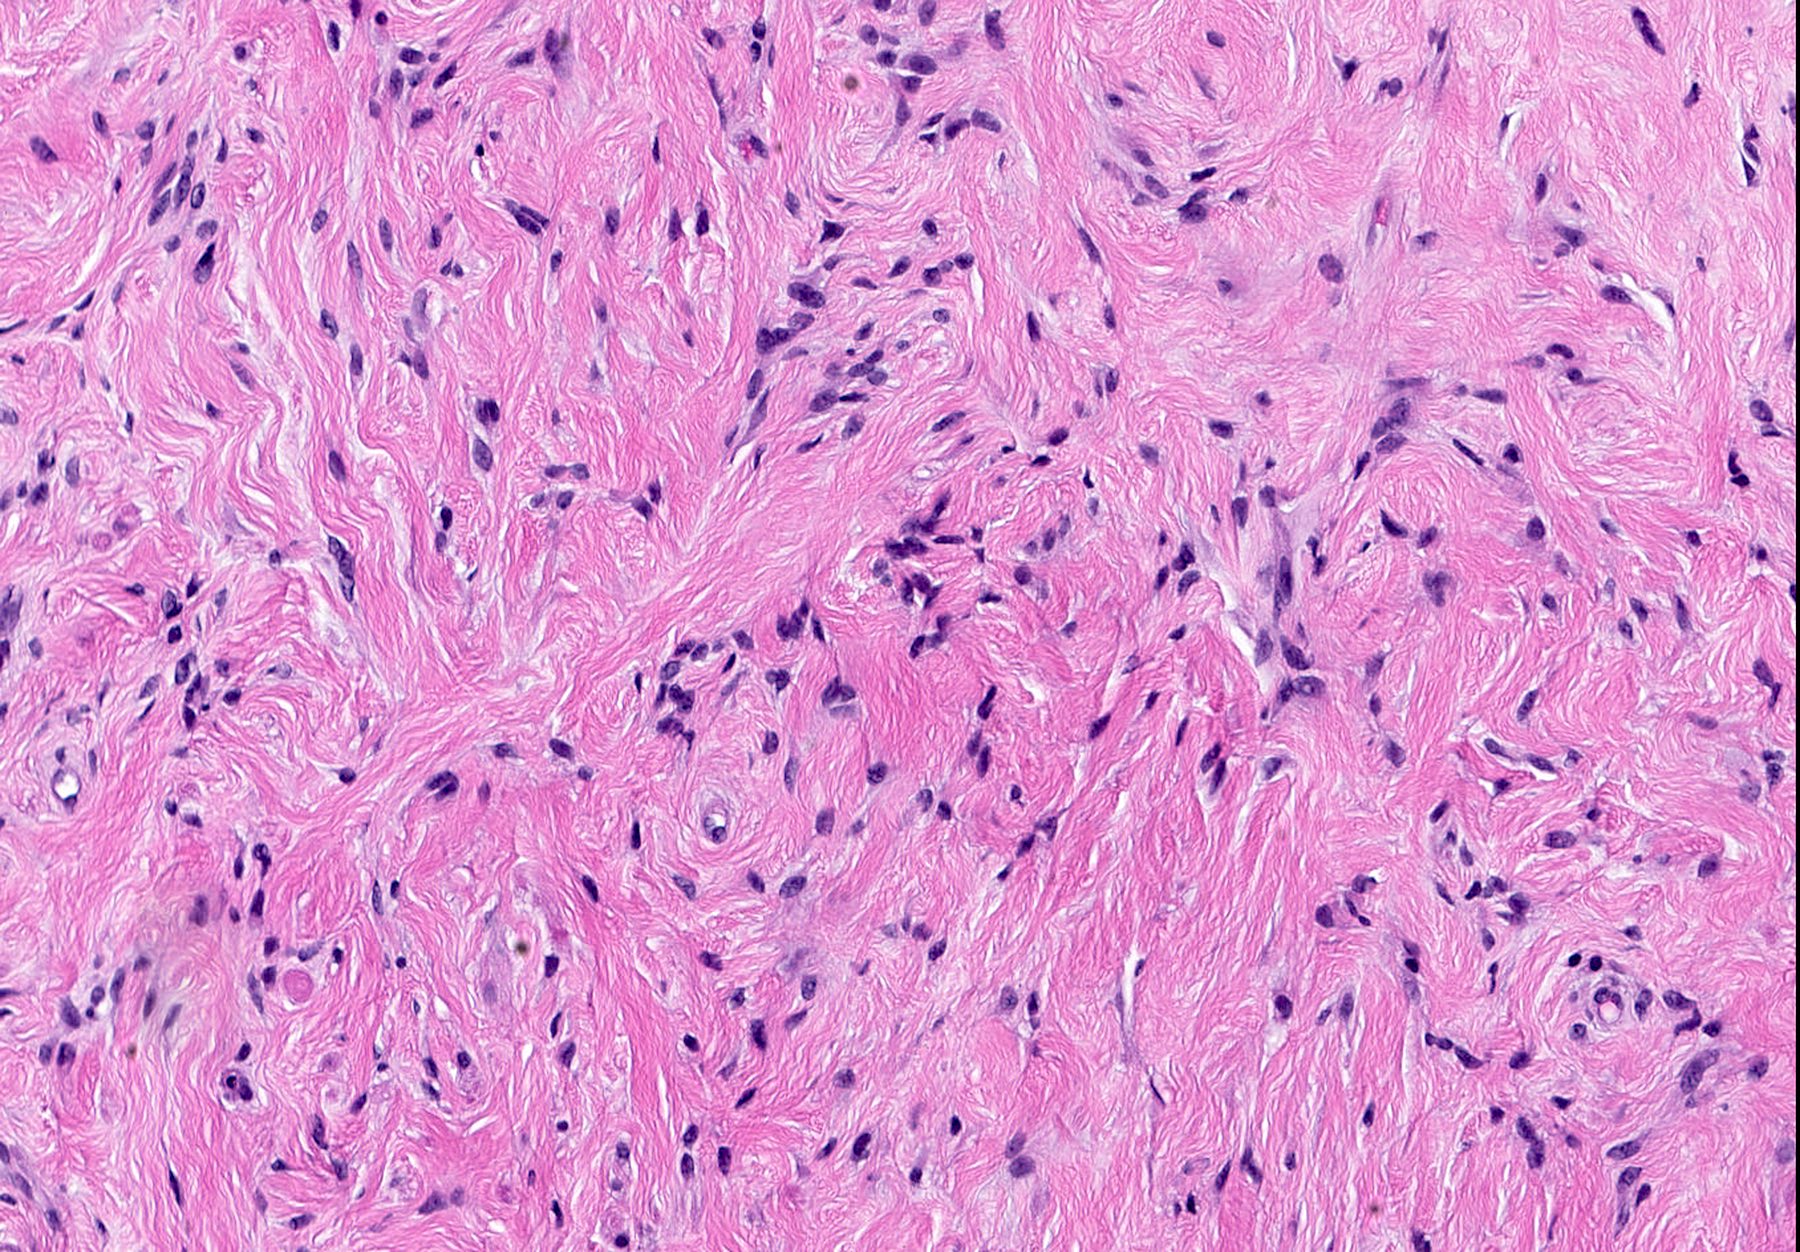

Microscopic (histologic) images

- Bland, uniform, short to elongated spindle cells arranged as short haphazard intersecting fascicles admixed with bands of hyalinized, brightly eosinophilic collagen and variable amounts of fat

- No more than mild nuclear atypia

- Mitoses usually absent, atypical mitoses and necrosis absent

- Focal myxoid stromal changes common

- Collagenized / fibrous: collagenous stroma predominates, may have hypocellular myofibroblastic spindle cell component